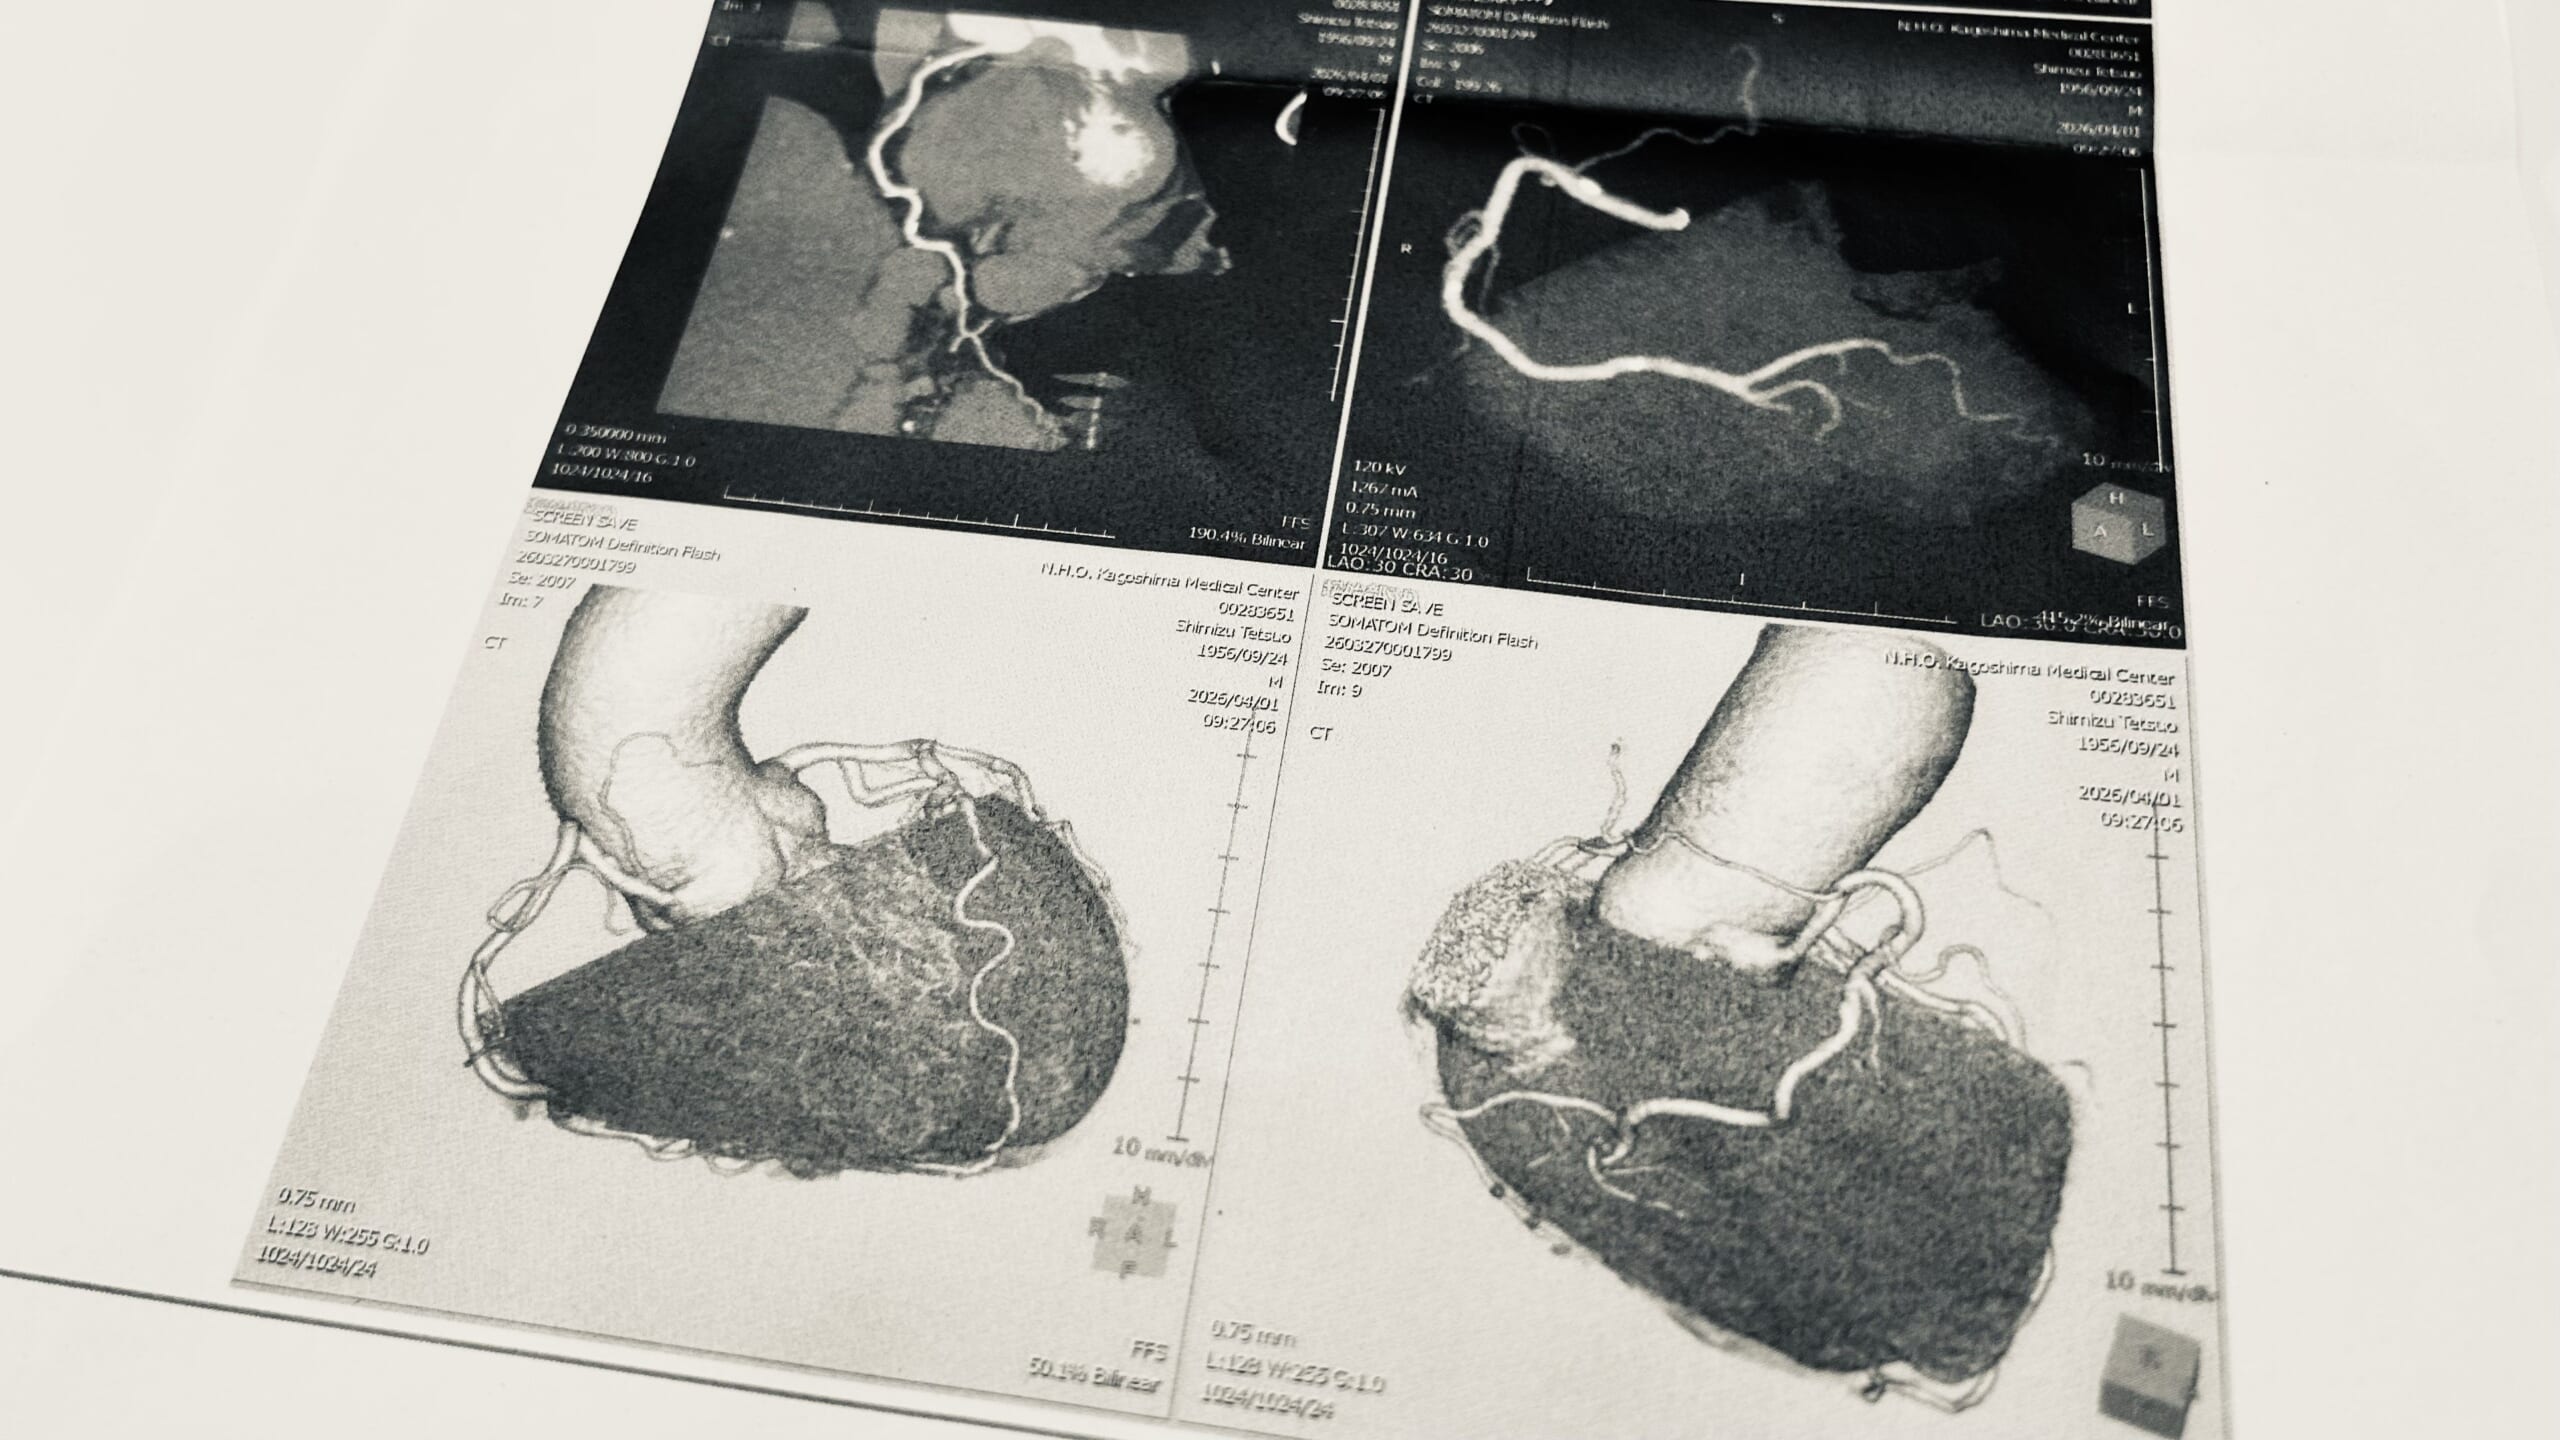

レントゲンと心臓エコーでは狭心症を疑うという結果でした。日を空けて心臓CTを。結果心臓左側の冠動脈に動脈硬化と血管が少々細くなっているところが見つかりましたが、血流自体は確保されていると。でもさらに詳しく調べるということで、写真展が終わってから心臓シンチという検査を受けることに。心臓を輪切りにして撮影するそうです。その結果で必要な処置を決めると。